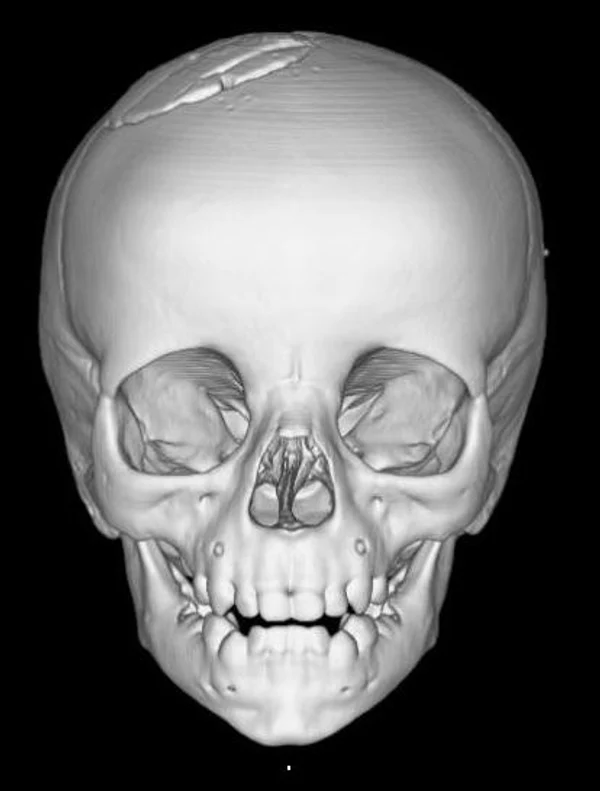

Удаление опухолей черепаВ качестве примера лечения пациентов с опухолями черепа привожу личное наблюдение пациента грудного возраста с опухолью черепа. В возрасте 1 мес. у ребёнка в затылочной области слева родителями обнаружено плотное образование диаметром 5 мм. За 3 мес. до госпитализации образование значительно увеличилось в размерах. При поступлении в возрасте 6 мес. в затылочной области слева (в проекции лямбдовидного шва) имеется безболезненное, плотное, неподвижное, бугристое образование размерами 5 х 4 х 2 см. При КТ и МРТ головы выявлена опухоль черепа в области астериона слева, обладающая преимущественно интракраниальным ростом (рис. 30 а). Ребёнку выполнено удаление опухоли черепа (рис. 30 б). Образовавшийся дефект черепа больших размеров закрыт перфорированной титановой пластиной (рис. 30 в). При наблюдении пациента в течении 2-х лет рецидива заболевания и деформации черепа не отмечалось.